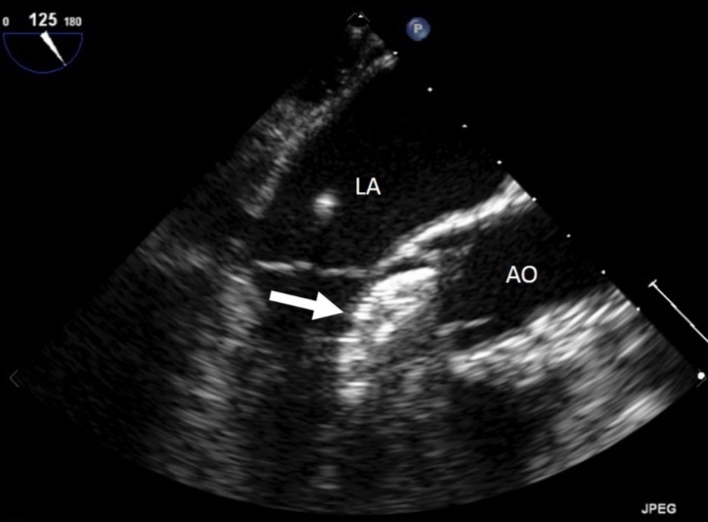

On examination, her heart rate was 71 beats per minute regular, blood pressure was 143/80 mm Hg, air saturation was 96% breathing ambient air and no fever. Jugular veins were not engorged. S1 and S2 were normal. There was a grade 3/6 ejection systolic murmur at right upper parasternal area. 24 hours ECG monitoring showed sinus rhythm. The neurological and pulmonary examination was normal. She underwent immediate transthoracic echocardiography and subcostal view showed a left-right shunt at the interatrial septum. Further evaluation revealed that the device embolized to the left ventricle and was lying in the left ventricular outflow tract with the distal extremity crossing the aortic ring. The device was displaced longitudinally with an important effect of stenosis. (Figure 1), (Figure 2). The entrapped device induced mechanical obstruction of the left ventricular outflow tract with a maximum/minimum gradients of 64/42 mmHg. The left ventricular function and size were normal. The mitral valve was normal with a minimal regurgitation. The right ventricle was mildly enlarged with normal function. The tricuspid valve function was normal. No pericardial effusion was detected. There was no gross thrombus deposition over the device in echography and no vegetation was detected anywhere.

Figure 1.Entraped Amplatzer ASD closure device in the left ventricular outflow tract. LA : left atrium, AO : aorta, arrow : ASD closure device.

Entraped Amplatzer ASD closure device in the left ventricular outflow tract. LA : left atrium, AO : aorta, arrow : ASD closure device.